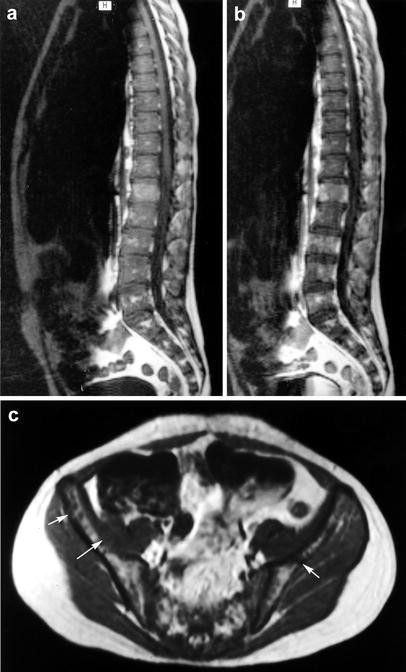

36+ Bone Leukemia Radiology Images. Leukemia is a hematological neoplasm characterized by the overproduction of immature (blasts) or abnormally differentiated cells of the hematopoietic system in the bone marrow that often. In leukemia, bone marrow infiltration usually occurs diffusely, with a diffuse decrease in the marrow.

Learn more about the causes, risk factors, symptoms, diagnosis, treatment types, and prognosis for acute lymphoblastic leukemia. Acute leukemia is a malignant neoplastic disease that arises from either the lymphoid cell line (acute lymphoblastic/lymphocytic/lymphoid leukemia, all) or the myeloid cell line (acute myeloid/myel. It is also possible to characterize leukemia based on whether or not the leukocyte count is altered (leukemic or aleukemic).